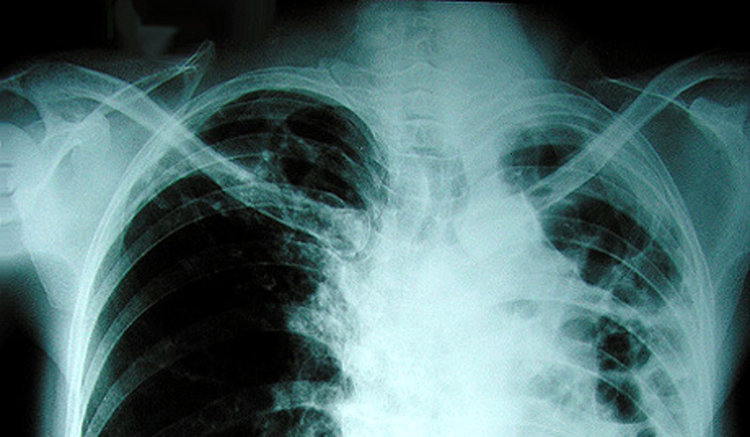

Седмица на отворените врати организира болницата в Кърджали от 19 до 23 юни във връзка с изпълнението на Националната програма за превенция и контрол на туберкулозата в България. Това съобщиха от здравното заведение.

Диабетици специалисти на пневмо-фтизиатричното отделение ще  извършват безплатно изследване на хора, които страдат от продължителна кашлица, често имат повишена температура,  имат  необяснима загуба на тегло.